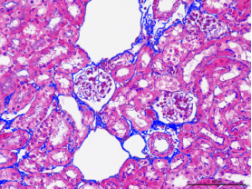

组织病理学平台

利用Image-pro-plus对病理染色结果半定量分析

利用Image-pro-plus软件,可以为您对各种动物疾病模型采取针对性染色,并对染色结果给出半定量分析,包括但不限于以下疾病模型:

1肾间质纤维化程度半定量分析